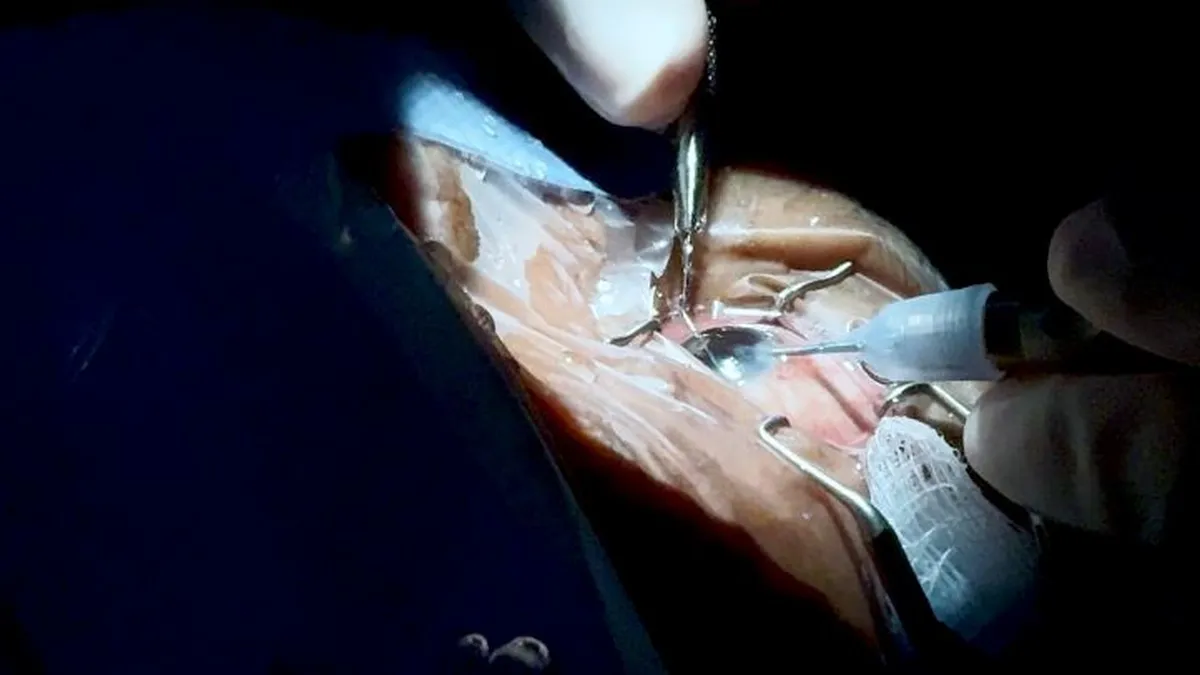

Policlínica de Betania realiza más de 250 cirugías de cataratas / Cortesía/ Caja del Seguro Social (CSS)

Policlínica de Betania realiza más de 250 cirugías de cataratas / Cortesía/CSS

Cada procedimiento tiene una duración de entre45 minutos y una hora y media, y se lleva a cabo en un quirófano especialmente acondicionado para este tipo de intervenciones dentro de la policlínica.